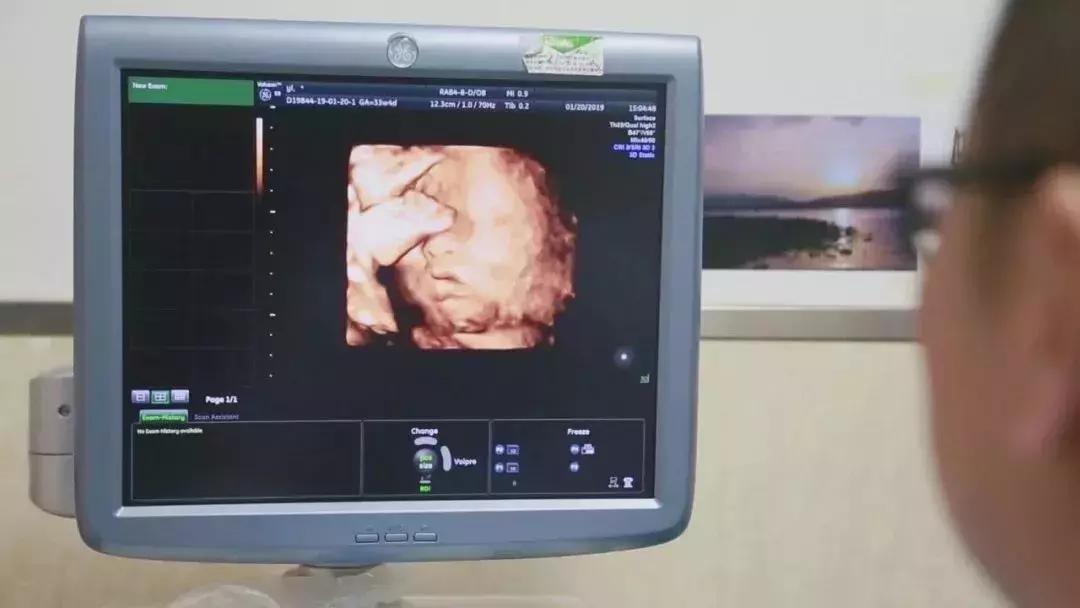

在对移植子宫连续监测后,为提高胚胎移植成功率,专家团队采取中西医结合的方法,改善杨华子宫内膜情况,为胚胎着床做好准备。2018年6月13日,妇产科王西林教授实时监测超声,在超声“慧眼”精确指引下,妇产科黄艳红教授小心翼翼地将冷冻胚胎植入移植的子宫内。

整个孕期,为避免出现并发症、确保母婴健康,妇产科、泌尿外科专家团队结合杨华身体情况,制定了个体化免疫抗排斥用药等方案,并定期进行超声、血药浓度、激素水平等监测。根据监测结果,实时调整用药,保证胎儿羊水、体重、胎心等生长发育指标处于正常范围。

足月的胎儿对移植子宫造成的压力,让分娩的风险成倍增加,陈必良教授团队选择在孕33+6周进行剖宫产手术,迎接这个新生命的到来。

2019年1月20日,陈必良教授主刀施行剖宫产手术,刘朵朵教授配合手术,麻醉科陈敏教授施行麻醉。术中,采取腹壁纵切口完成子宫下段剖宫产,探查确认移植的子宫动静脉缝合口、韧带等恢复良好,手术历时1小时6分钟圆满成功。

新出生的宝宝身体各指标正常,体重2kg,身长48cm,Apgar’s评分:1分钟10分,5分钟10分,10分钟10分。剖宫产手术结束后,专家团队没有立即摘除子宫,小两口还计划着孕育二胎。